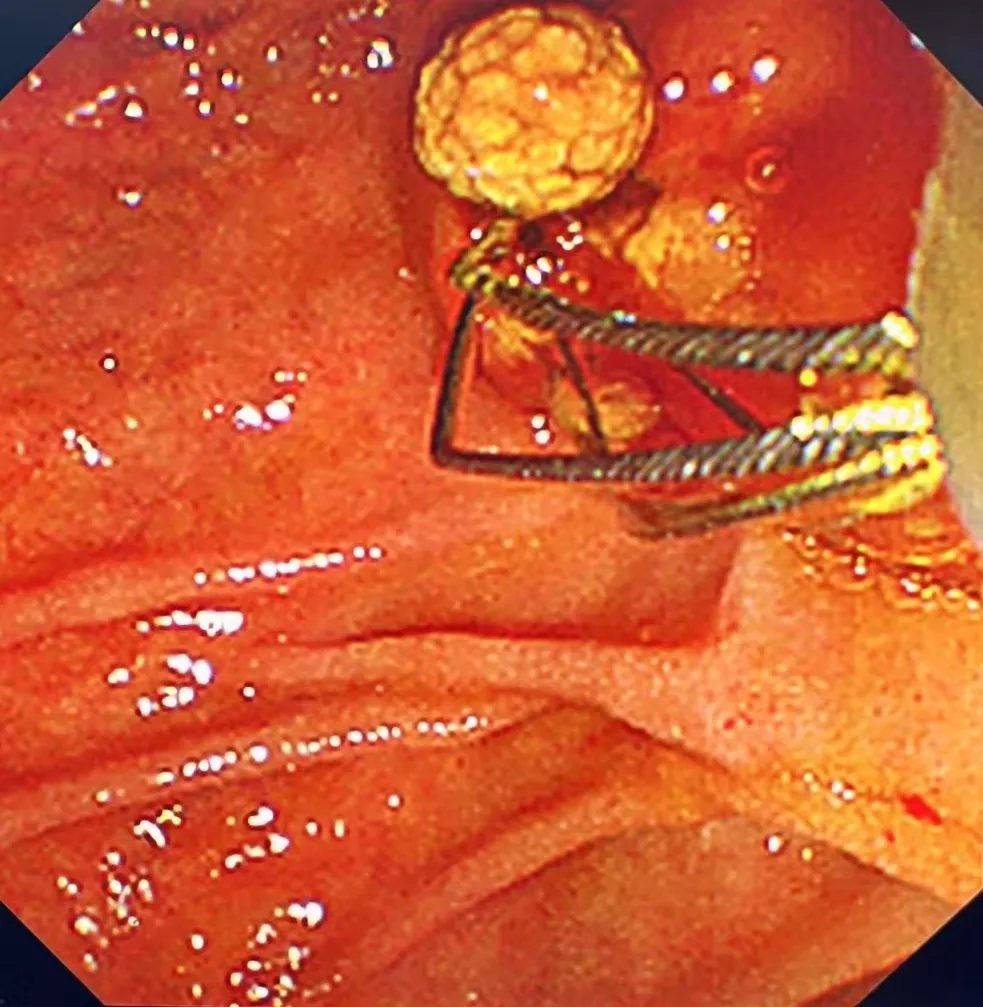

40分钟微创手术化解危机

明确胆总管结石诊断后,医护人员立即为周同学实施了经内镜逆行胰胆管造影取石术(ERCP)。这项技术无需开腹,就像做胃镜一样,通过口腔-食道-胃-十二指肠的自然腔道抵达胆管开口,再使用专用器械(取石网篮、球囊等)直接取出结石。

整个手术过程仅耗时40分钟,胆道梗阻和感染风险被迅速解除,周同学体表没有留下任何伤口。

术后,周同学的黄疸明显消退,腹痛也消失了。他恢复很快,第二天即可下床活动。

一场凶险的胆道梗阻,就这样在微创内镜的技术下,被轻松化解。